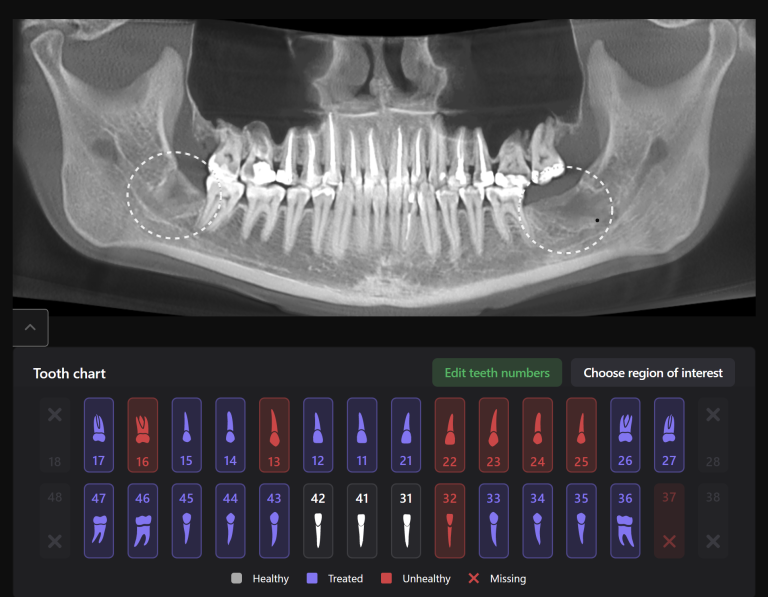

Diagnocat radiological report features an “Conditions with low probability” function. In this mode, teeth marked as “Low probability” are highlighted in yellow. Conditions such as caries and periapical lesions with a probability ranging from 30% to 50%

For example, in the area of tooth 22 (Universal 10), there is a label indicating “signs of caries.” However, they are poorly visualized at the CBCT

During the clinical examination, the presence of caries on the mesial surface of tooth 22 (Universal 10) has been confirmed

Additionally, thanks to the “Conditions with low probability,” signs of caries have been detected on the distal surface of tooth 24 (Universal 12)

If the probability percentage is over 50%, the teeth are highlighted in red, and the report contains information about the localization and depth of the lesions

The presence of caries on the distal and mesial surfaces of tooth 47 (Universal 31) has been clinically confirmed